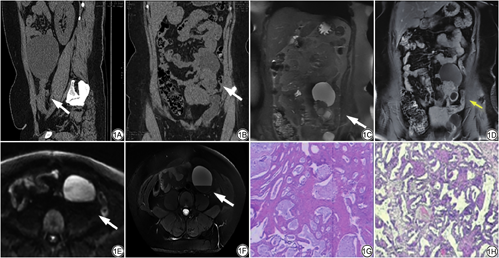

患者女,42岁,左卵巢子宫内膜样腺纤维瘤。A:2016年腹盆CT平扫:左腹部及左附件区囊状低密度影,内密度较均匀,病灶以较窄颈与左附件区相连(白箭);B:2021年腹盆平扫:腹腔左侧部团块状囊实性软组织密度灶,边界清,内见液液平面(白箭);C、D:2021年MRI示腹腔左侧部团块状囊实性信号影,T2WI示囊实性肿块(白箭),动态增强扫描病灶囊壁及实性部分可见轻度强化(黄箭);E:DWI示病灶大部(白箭)呈高信号;F:T2WI压脂病灶大部(白箭)呈高信号;G:2016年病理学标本(HE ×40),肿瘤呈腺管样,腺上皮为单层柱状上皮;H:2021年病理学标本(HE ×40),肿块部分区腺体拥挤,形态欠规整

Patient, female, 42 years old, endometrioid adenomoma of the left ovary. A: In 2016, abdominal pelvic CT plain scanning: cystic low density shadow of the left abdomen and left attachment area, uniform internal density and narrow neck connection to the left attachment area (white arrow). B: In 2021, pelvic plain scanning: solid soft tissue density stove in the left side of the abdominal cavity, with clear boundary, and liquid level (white arrow). C, D: In 2021, the left abdomen in MRI, T2WI showed cystic solid mass (white arrow), mild enhancement (yellow arrow) in the solid wall of the lesion. E: DWI (white arrow) showed a high signal of the lesion. F: T2WI showed a high signal. G: In 2016, pathology specimen (HE ×40), the tumor was adenoidal and single-layer columnular epithelium. H: In 2021, pathology specimen (HE ×40), the gland was crowded and unregulated in part of the mass.